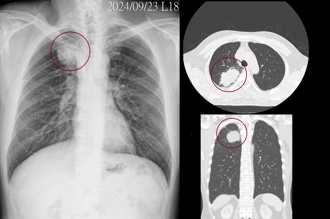

• 不菸不酒!50歲男「肺部6公分腫瘤」到處轉移 醫師分析最大原因

不菸不酒!50歲男「肺部6公分腫瘤」到處轉移 醫師分析最大原因

肺癌是我國癌症發生率及死亡率排名第一的疾病。胸腔科醫師蘇一峰今(8)日分享,有位50歲男性不菸不酒、沒有任何不適症狀,沒想到拍攝X光照後卻發現肺部存在6公分的腫瘤,肺癌更到處轉移,感嘆「空氣污染是台灣目前不抽菸得到肺癌的主要原因」。